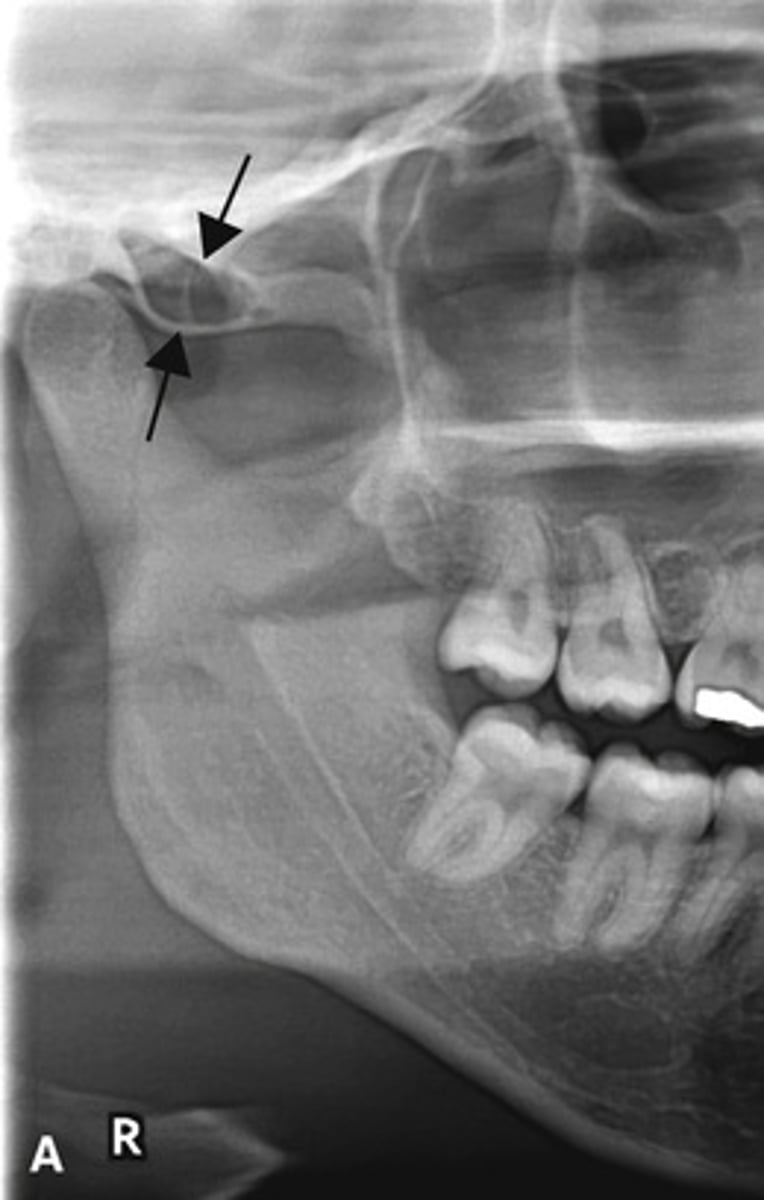

Patient has DJD.

The top images show the subchondral/ Ely cyst, a pseudocyst of connective tissue, granular tissue and osteoid, the bottom images show the same patients left side with broad erosion, a lack of cortication, loss of joint space.

What is the diagnosis of the patient based off these radiographs and what are the features? (Top images = patients right condyle) (bottom images= same patients left condyle)